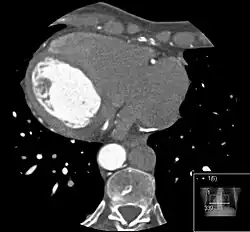

Azygoskontinuität der V. cava inferior in der Computertomographie links axial mit Darstellung des Venensterns der Leber (im Prinzip normal) und der deutlich erweiterten V. azygos. Bild auch mit Cavathrombose vereinbar, bei der die Umleitung über die Azygos erfolgt. Rechts coronar mit Darstellung des Zusammenflusses von Nierenvenen (in diesem Schnitt nur rechte angeschnitten) und Vv. iliacae. (Arterielle Kontrastmittelphase, daher ist die Aorta deutlich heller.)